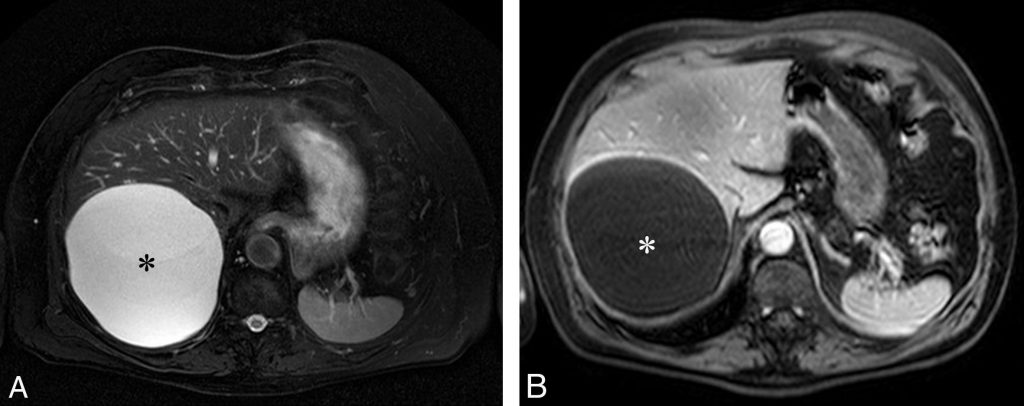

- en franc hypersignal en pondération T2 et sans prise de contraste après injection (figure 16.11).

Fig. 16.11. IRM d’un kyste hépatique typique du foie droit. Il apparaît hyperintense en pondération T2 (A), comparable au liquide cérébrospinal. Sur une séquence en pondération T2 seule, la différence avec un hémangiome est difficile. À la différence de ce dernier, en pondération T1 après injection (B), le kyste présente un hyposignal franc et ne se rehausse pas.

Source : CERF, CNEBMN, 2022.